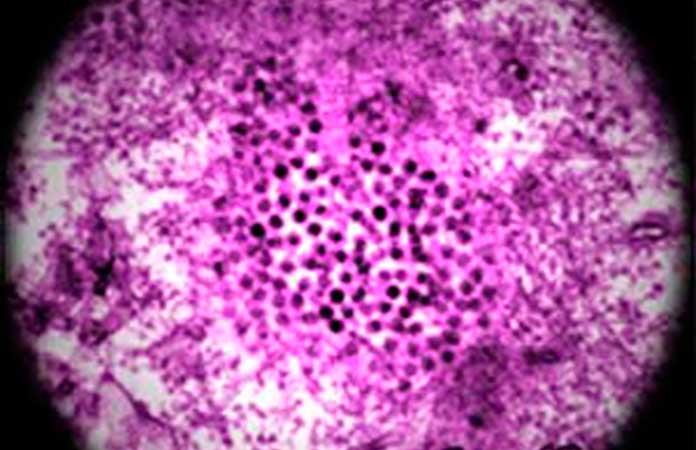

El Virus del Nilo Occidental es una enfermedad que se transmite por la hembra infectada del mosquito común del género 'Culex', que se alimentan de sangre de aves. Humanos y équidos son las especies de mamíferos más susceptibles a la misma.